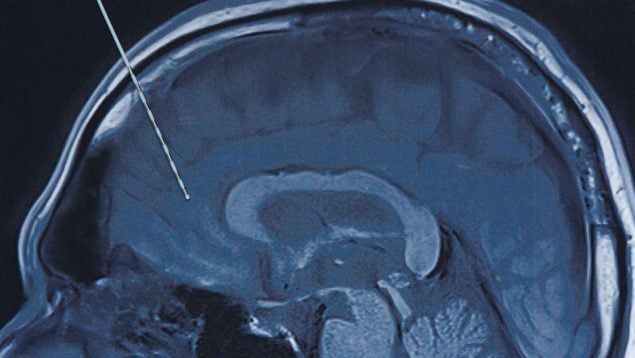

El procedimiento consistió en colocar una fina lámina con 253 electrodos sobre la corteza cerebral encargada del lenguaje. Estos electrodos captan señales neuronales que, mediante algoritmos avanzados, se traducen en palabras que Ann intenta formar mentalmente. Para que su voz sonara lo más natural posible, los investigadores entrenaron el sistema con grabaciones reales de su voz tomadas de un video familiar. El resultado: una comunicación fluida, casi instantánea, que décadas atrás habría parecido imposible.

Otro avance significativo proviene de un equipo de la Universidad de Washington, donde se desarrolló un implante diseñado para estimular zonas cerebrales afectadas por el derrame y ayudar al cerebro a «reconectarse». El dispositivo, formado por láminas de silicona ultrafinas, no solo detecta la actividad cerebral, sino que también aplica impulsos eléctricos cuidadosamente programados.

Estas señales buscan potenciar la plasticidad neuronal y facilitar la recuperación del movimiento en las extremidades afectadas. El implante se comunica de forma inalámbrica con un sistema externo que analiza los patrones cerebrales y ajusta la estimulación en tiempo real, complementando así la rehabilitación física tradicional. Aunque se retira tras varios meses, las mejoras pueden mantenerse a largo plazo, lo que abre un campo nuevo en las terapias post-ictus.